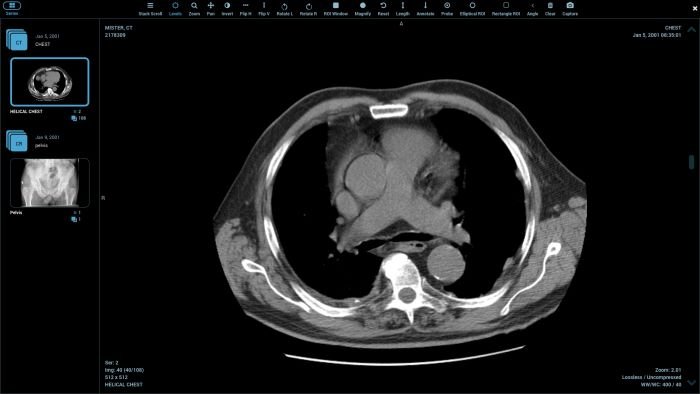

Стандарт позволяет организовать цифровую связь между различным диагностическим и терапевтическим оборудованием, использующимся в системах различных производителей. Рабочие станции, Компьютерные (КТ) и Магнитно-резонансные Томографы (МРТ), микроскопы, УЗ-сканеры, общие архивы, хост-компьютеры и мэйнфреймы от разных производителей, расположенные в одном городе или нескольких городах, могут "общаться" друг с другом на основе DICOM с использованием открытых сетей по стандартным протоколам, например TCP/IP.

Популярные программы для просмотра DICOM-файлов (Windows, macOS, iOS, Android и Linux)

Видео-обзор лучших программ для просмотра DICOM-файлов